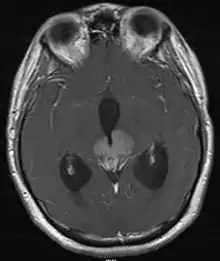

На основании этих проявлений, врач проводит исследования крови, компьютерную томограмму, МРТ, эхо-энцефалографию.

Герминома, среди всех опухолей мозга, занимает лишь 2 %, диагностируется в возрасте 10-12 лет, реже к 20 годам. Этому заболеванию подвержены чаще мужчины[5]. При диагностики данного заболевания, характерны симптомы гипофизарно-гипоталамической недостаточности (замедление роста, гипопитуитаризм, несахарный диабет). При исследовании с помощью рентгена данная опухоль может не определяться, особенно на ранних стадиях. При лабораторных исследованиях часто тестируются сывороточные и спинномозговые опухолевые маркеры альфа-фетопротеина (АФП) и бета-ХГЧ. Истинные герминомы не связаны с этими маркерами. Нергерминоматозные опухоли могут быть связаны с повышенными маркерами, такими как AFP, с эмбриональными клеточными карциномами и незрелыми тератомами и бета-ХГЧ, которые встречаются при хориокарциномах. У 1 до 15 % гермином может быть получен низкий уровень бета-ХГЧ. HCG-секретирующие герминомы могут быть более агрессивными, чем несекретирующие.